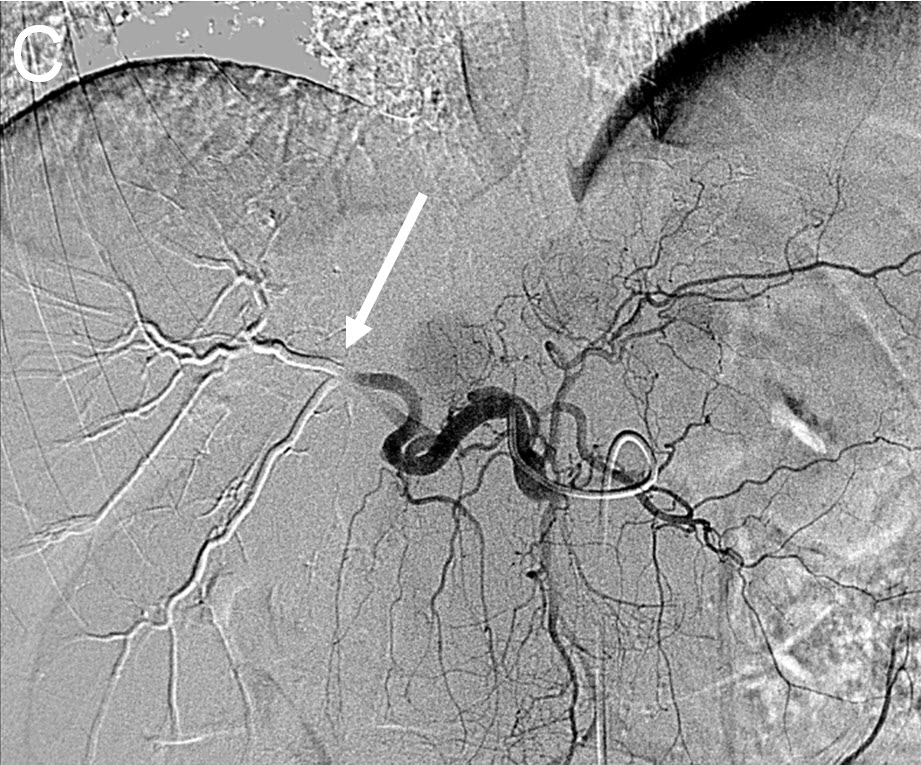

| (C) Angiogram after right hepatic artery(white arrow) embolization using Drug Eluting Beads (DEB TACE) |